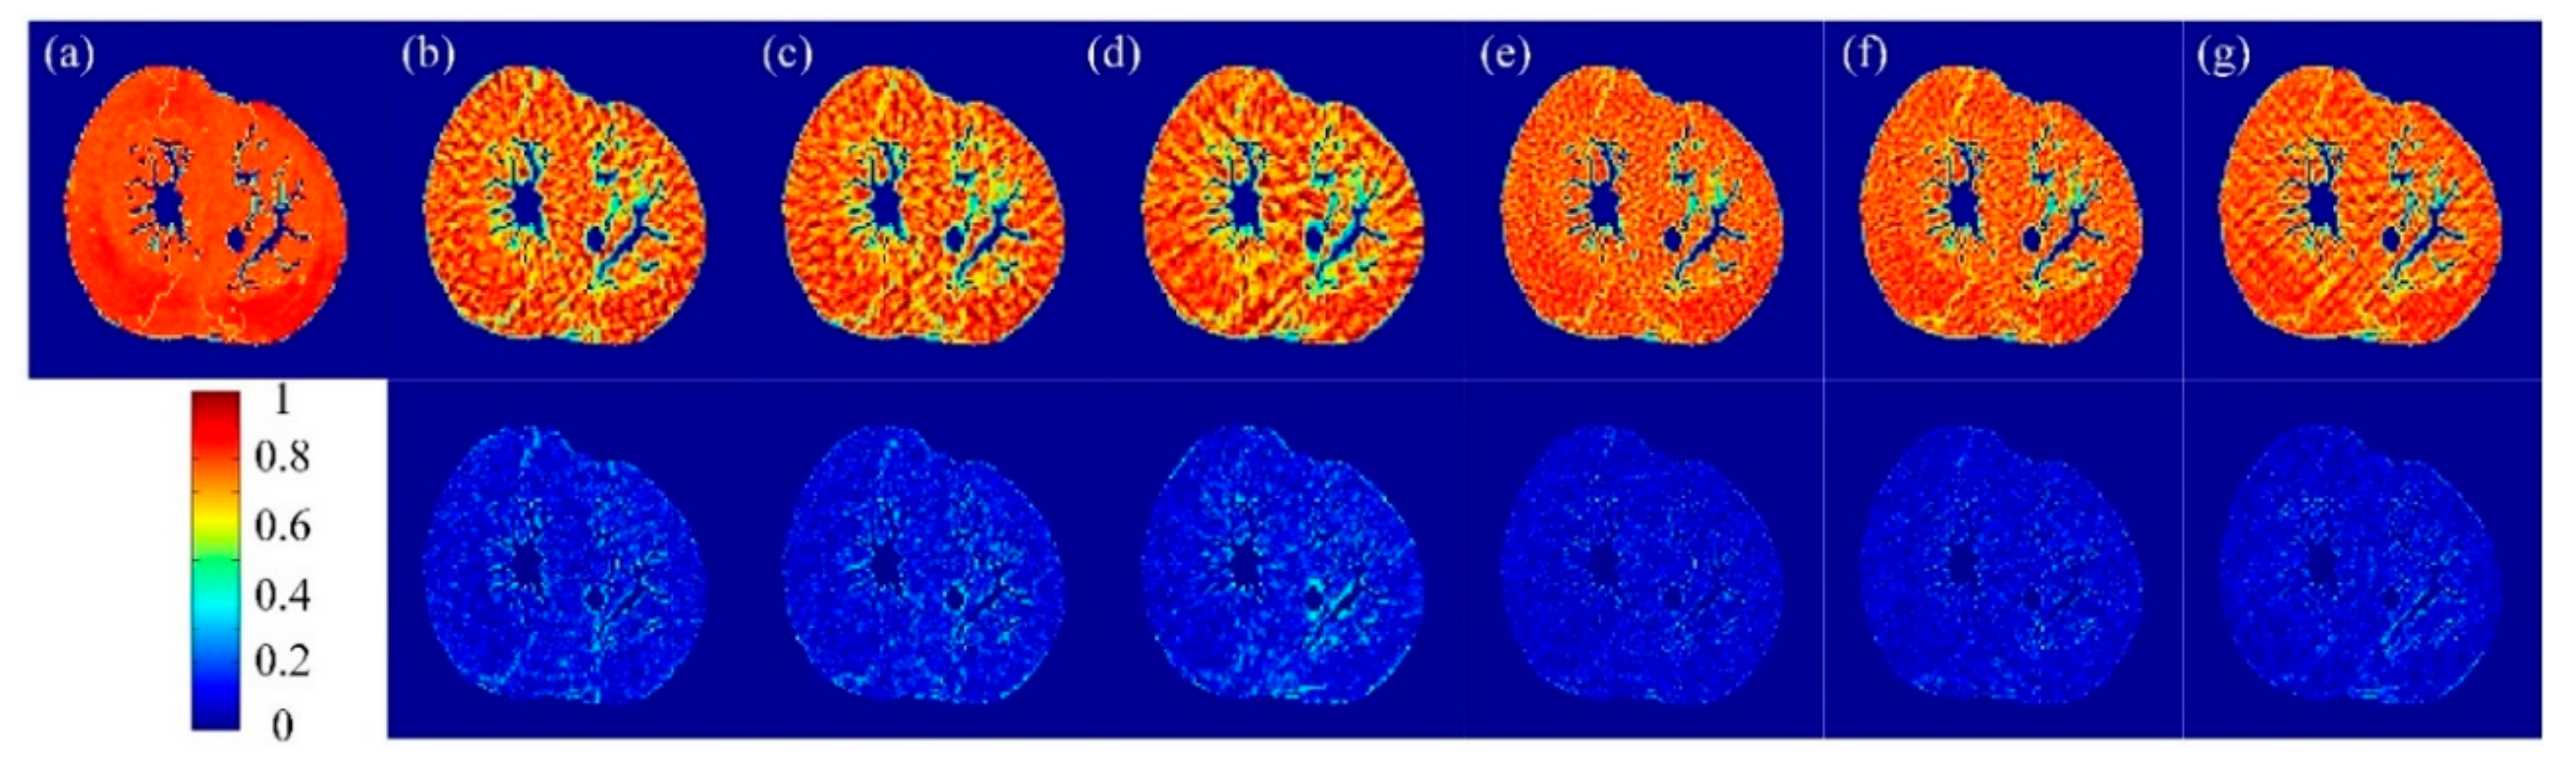

3.1. Visual and Quantitative Comparison